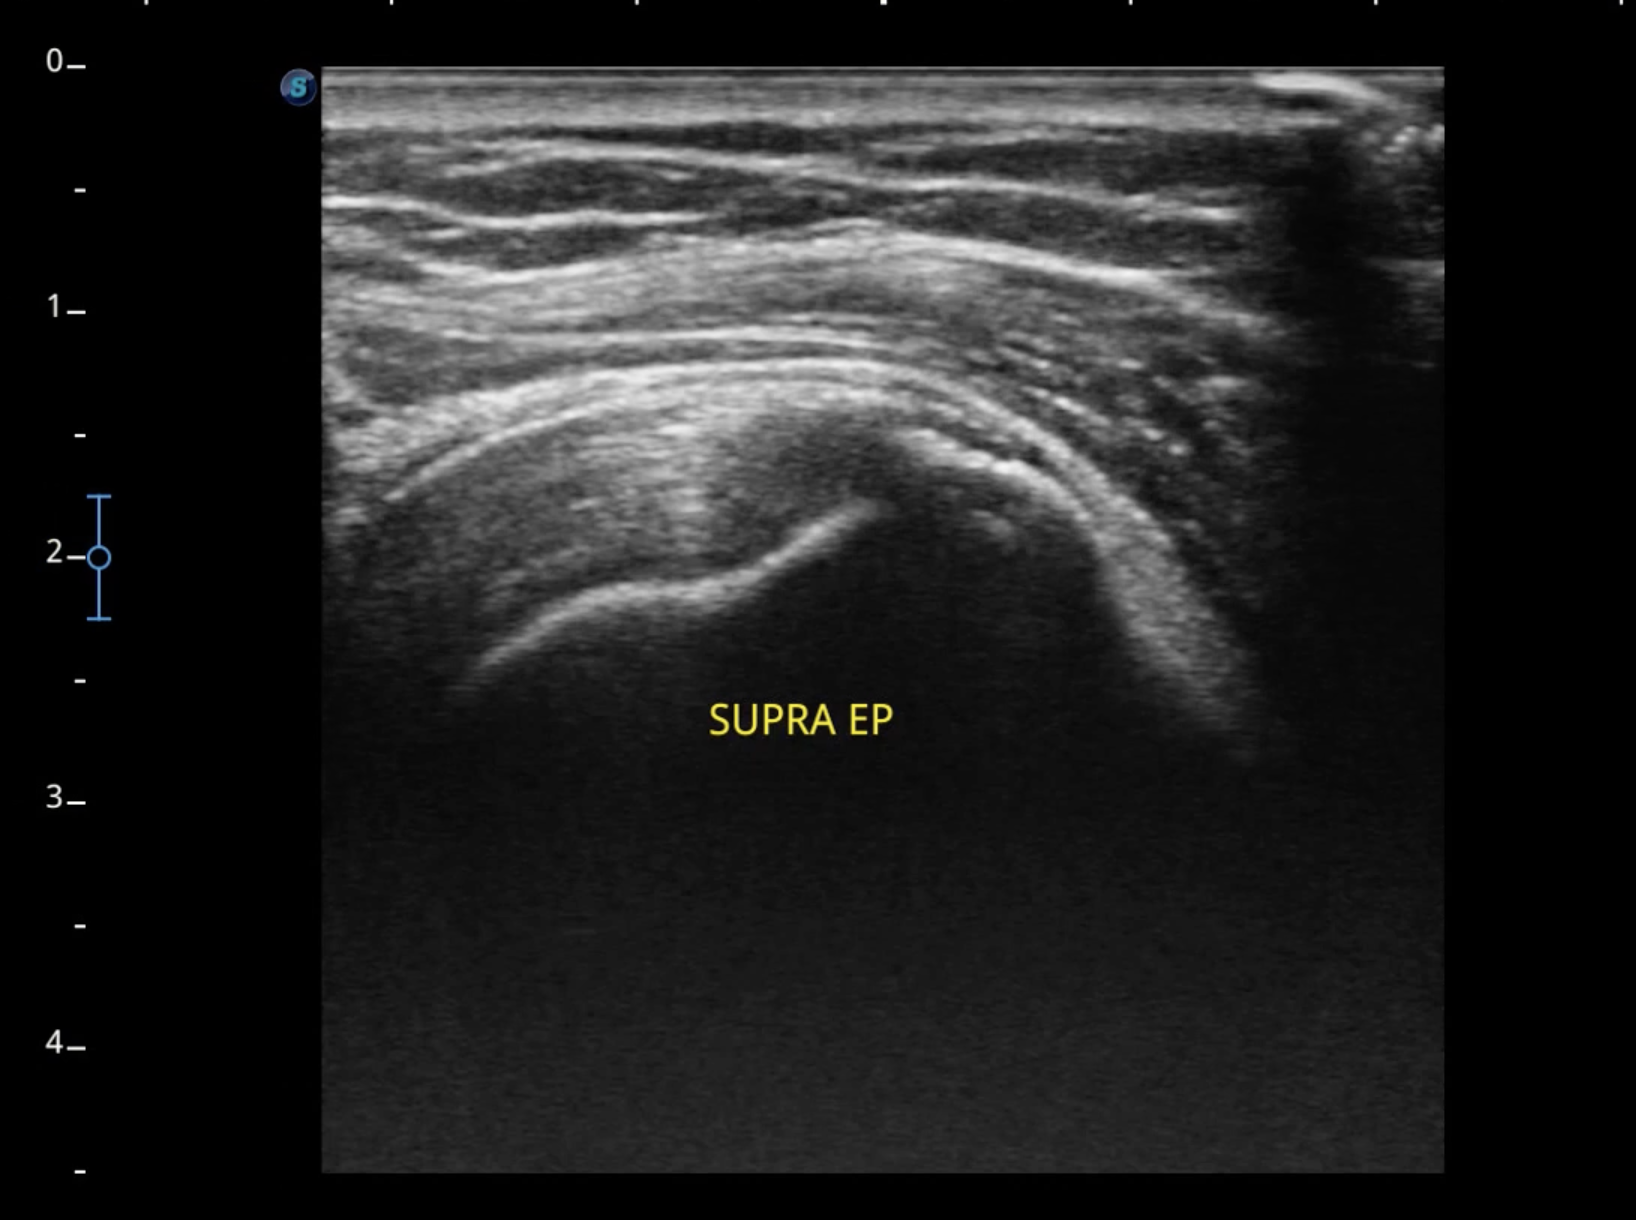

Bursite deltoidienne en échographie . Dans cet article, nous explorerons les causes, les. Le diagnostic de la tendinopathie du supra-épineux et de la bursite sous acromio-deltoïdienne se fait souvent par une combinaison d'examens cliniques et d'imagerie

Source: ravpaczga.pages.dev PPT Rupture de la coiffe des rotateurs PowerPoint Presentation ID1274128 , Cette bourse est une poche liquidienne qui s'interpose entre la voûte osseuse sous-acromiale et les muscles de la coiffe des rotateurs pour y favoriser le glissement lors des mouvements de l'épaule. L'IRM et l'échographie sont généralement utilisés pour visualiser les tendons et les bourses de l'épaule pour détecter toute inflammation ou déchirure.

Source: analistbfg.pages.dev Bursite deltoidienne en échographie , Le diagnostic de la tendinopathie du supra-épineux et de la bursite sous acromio-deltoïdienne se fait souvent par une combinaison d'examens cliniques et d'imagerie Il faut y penser en cas de douleurs chroniques de l'épaule